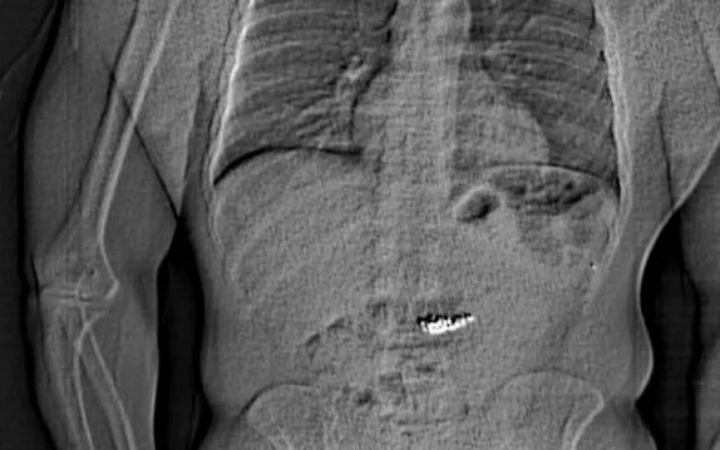

পুলিশ পরে একটি এক্স-রে ছবি প্রকাশ করে, যাতে দেখা যায় একজন ব্যক্তির পেটে এক ধরনের বস্তু রয়েছে। গিল্ডারকে হাসপাতালে নিয়ে প্রায় দুই সপ্তাহ ধরে নজরদারিতে রাখা হয়, যতক্ষণ না দুলগুলো উদ্ধার করা যায়। ১২ মার্চ চতুর্থ দুলটিও উদ্ধার করা হয়।